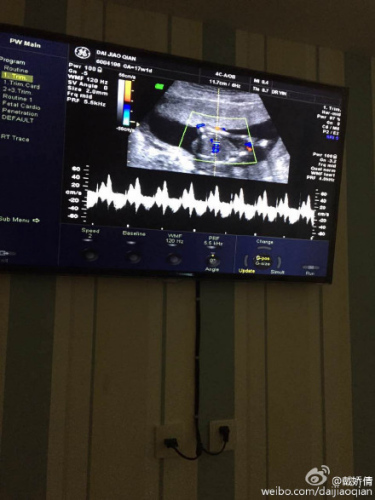

戴娇倩承认怀孕 晒b超图:新的身份,新的生命